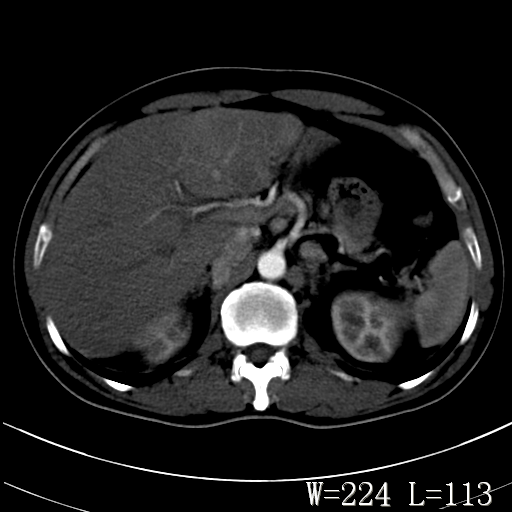

标题: CT27340:肝脏病变?

男,45岁,发热、乏力半月,午后为主。

对比剂快进快出,首先考虑肝左叶巨块型肝癌。

其次,感染性病变,如肝脓疡不排除。

蜂巢,肝脓肿

蜂巢状,支持!肝脓肿的诊断。